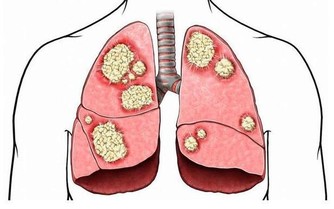

幽門螺桿菌:經口腔進入人體,是目前所知能夠在人胃中生存的唯一微生物種類。幽門螺旋桿菌病包括由幽門螺旋桿菌感染引起的胃炎、消化道潰瘍、淋巴增生性胃淋巴瘤等。幽門螺旋桿菌病的不良預後是胃癌。

幽門螺桿菌它會引起胃黏膜輕微的慢性發炎,甚或導致胃及十二指腸潰瘍與胃癌。